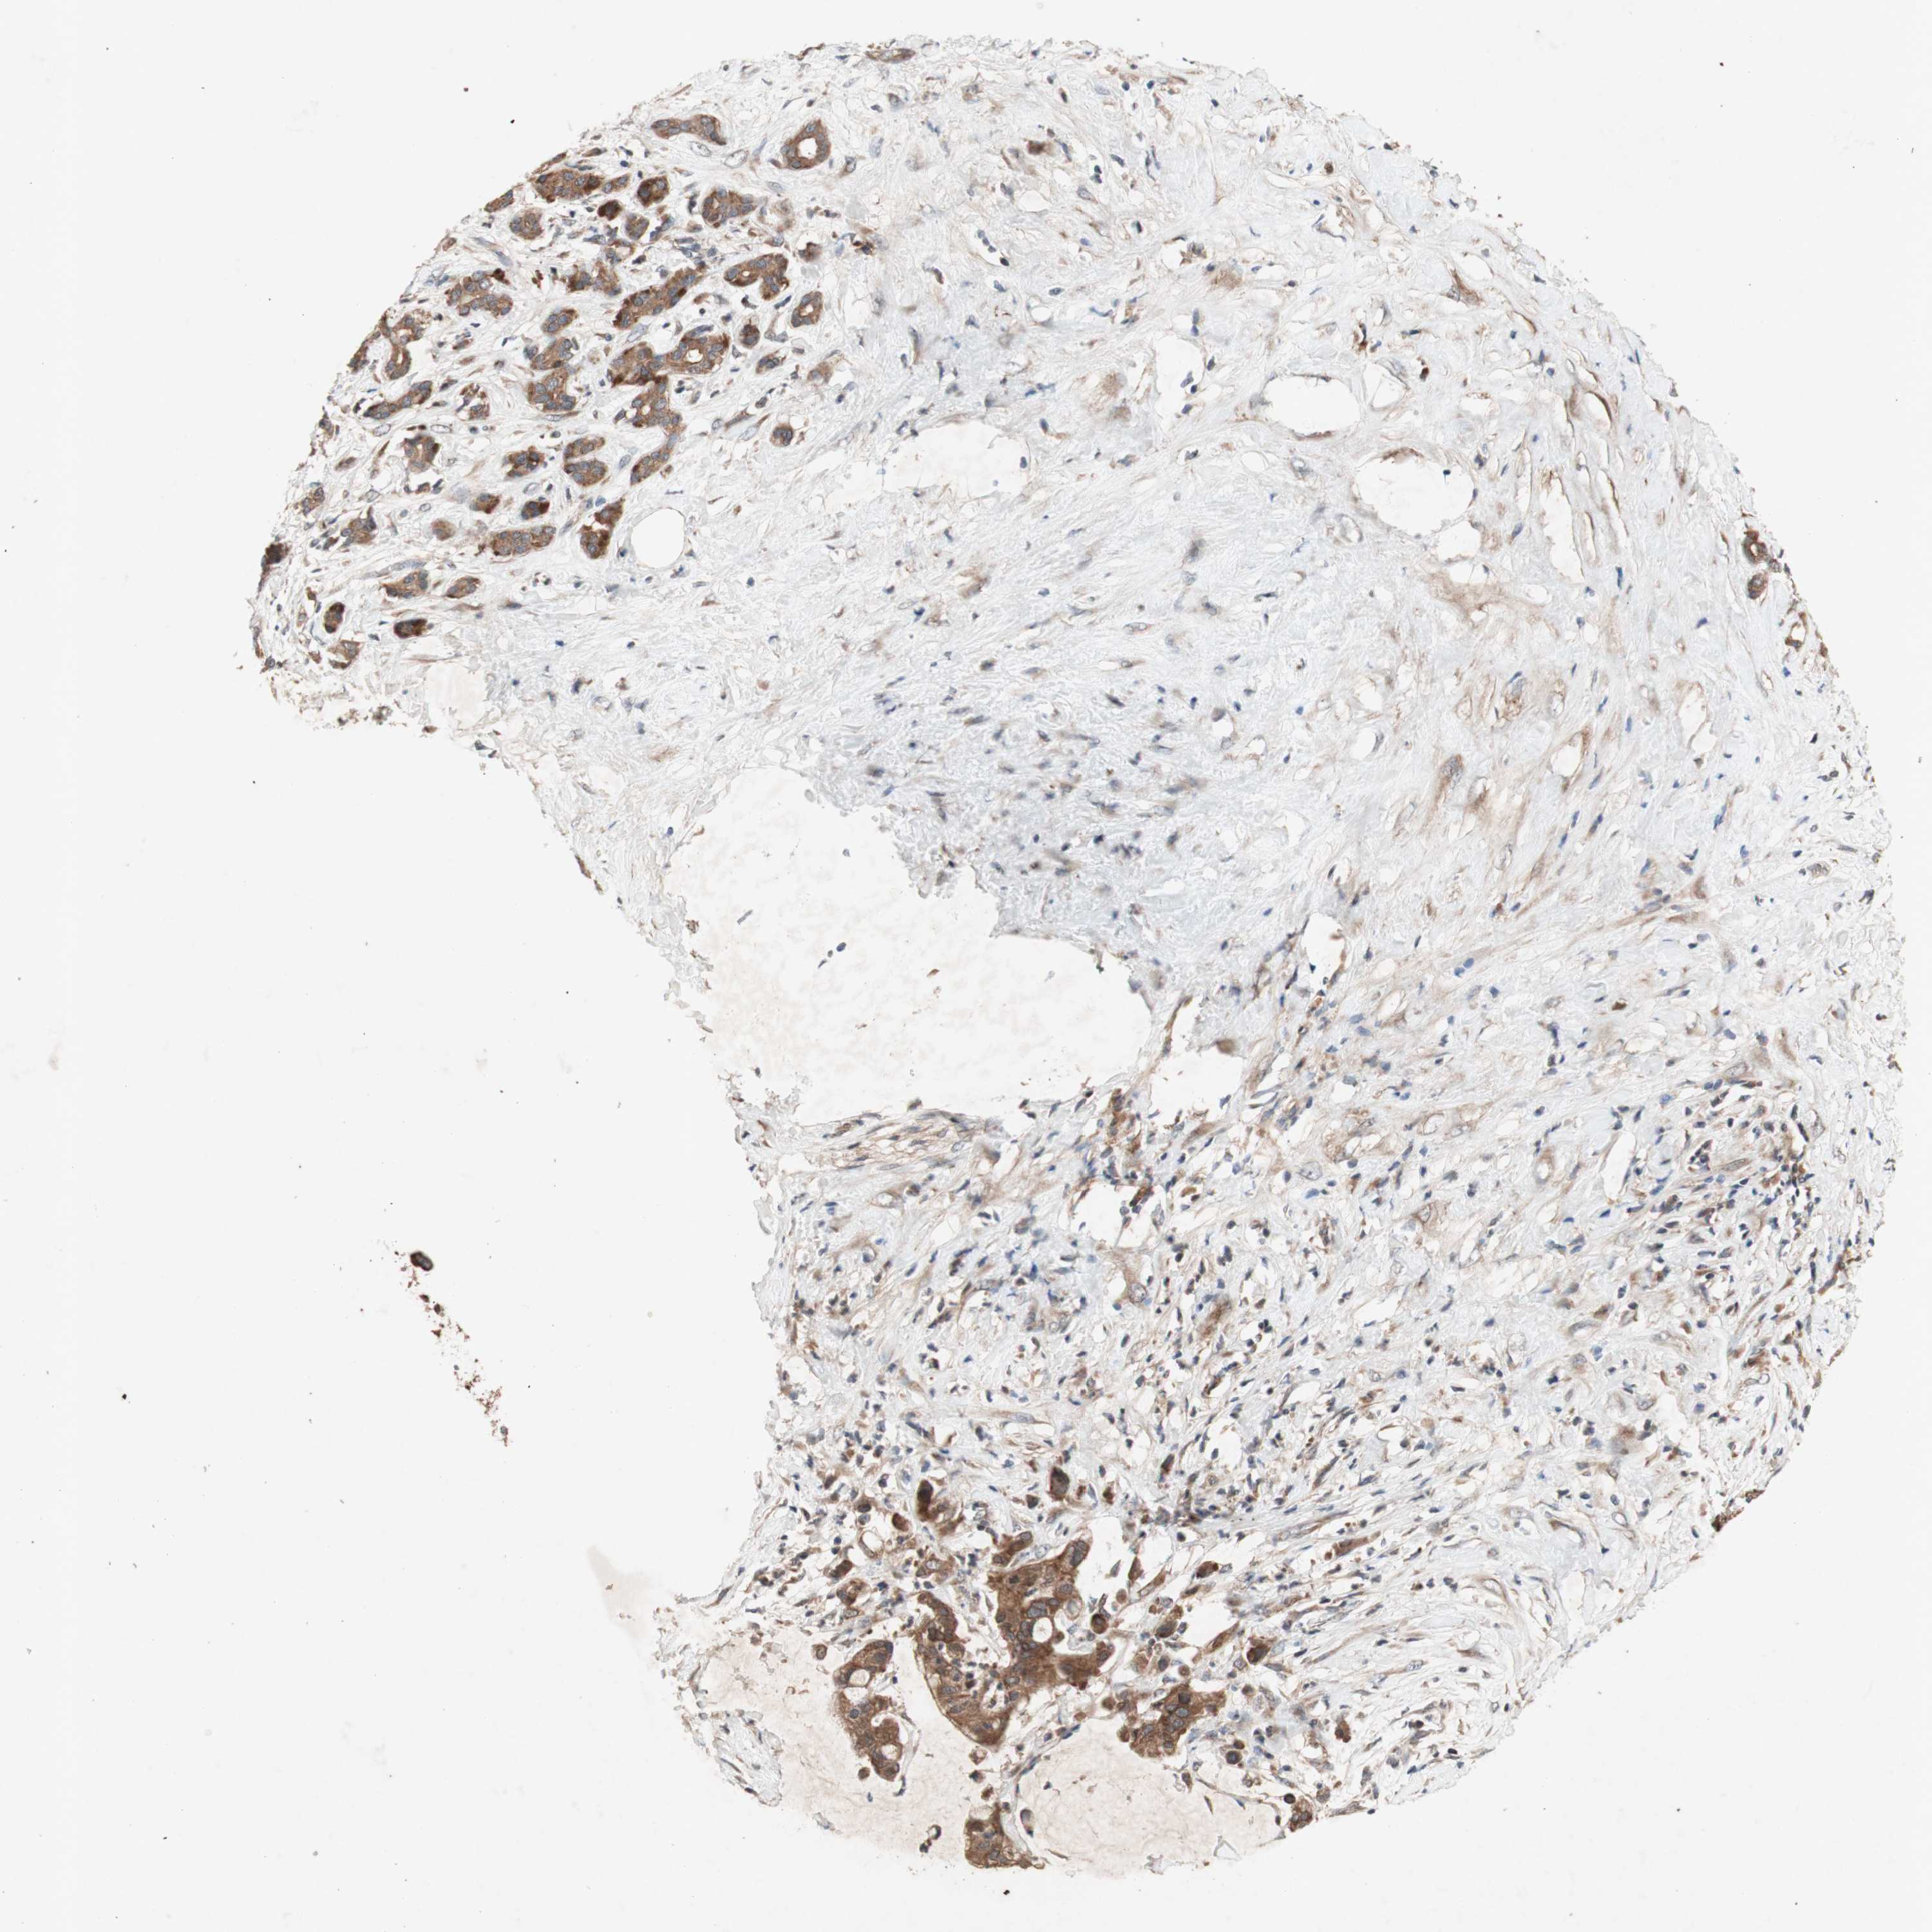

PANCREATIC CANCER - Protein expressioni

A mouse-over function shows sample information and annotation data. Click on an image to view it in a full screen mode. Samples can be filtered based on level of antibody staining by selecting one or several of the following categories: high, medium, low and not detected. The assay and annotation is described here.

Note that samples used for immunohistochemistry by the Human Protein Atlas do not correspond to samples in the TCGA dataset.

Antibody stainingi

Antibody staining in the annotated cell types in the current human tissue is reported as not detected, low, medium, or high, based on conventional immunohistochemistry profiling in selected tissues. This score is based on the combination of the staining intensity and fraction of stained cells.

Each image is clickable and will lead to virtual microscopy that enables deeper exploration of all samples and also displays staining intensity scores, fraction scores and subcellular localization as well as patient and tissue information for each sample.

Antibody HPA046841

Antibody HPA052867

Antibody CAB009746

Staining

High

Medium

Low

Not detected

Intensity

Strong

Moderate

Weak

Negative

Quantity

>75%

75%-25%

<25%

None

Location

Nuclear

Cytoplasmic/membranous

Cytoplasmic/membranous,nuclear

Adenocarcinoma, NOS

Adenocarcinoma, metastatic, NOS